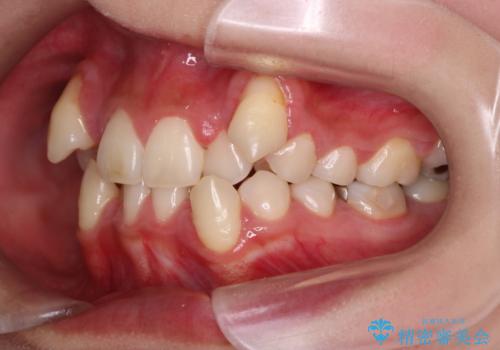

【抜歯矯正】犬歯抜歯による矯正。八重歯を治したい

- 八重歯を主訴に来院された患者様です。

インビザラインによる矯正を希望され、今回は移動距離が少なくなるように犬歯を抜歯する治療計画としました。

抜歯矯正において、通常では4番(第一小臼歯)が抜歯の対象となることが多いのですが、今回は3番(犬歯)の歯肉退縮や装置の特性を考慮した治療計画となります。